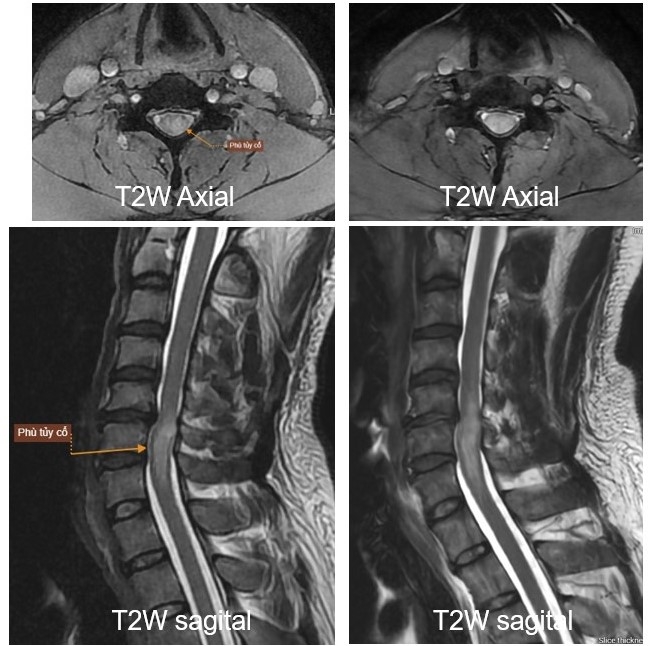

| Hình ảnh chẩn đoán qua chụp MRI tại Bệnh viện Mặt Trời |

Anh T. (46 tuổi) nhập viện trong tình trạng tê bì hai tay kéo dài, yếu dần hai chân, giảm cảm giác từ ngang ngực trở xuống và rối loạn đại tiện. Sau thăm khám, các bác sĩ Bệnh viện Mặt Trời chẩn đoán, xác định anh T. có u nội tủy chèn ép tủy sống, diễn tiến nặng và nhanh dù đã điều trị nội khoa nhiều tháng trước đó. Anh T. cho biết, ban đầu các triệu chứng chỉ giống như mỏi cổ-vai-gáy thông thường. Anh đã đi khám và chụp chiếu ở nhiều nơi từ năm ngoái nhưng không phát hiện ra bệnh. Khi tình trạng tê bì tăng nặng, anh đến khám tại Bệnh viện Mặt Trời vì biết đến các hệ thống chụp MRI, CT- Scan hiện đại tại đây đều là thiết bị thế hệ mới nhất. May mắn, các bác sĩ chẩn đoán hình ảnh tại đây đã giúp anh phát hiện chính xác khối u nội tủy, để có hướng điều trị dứt điểm.